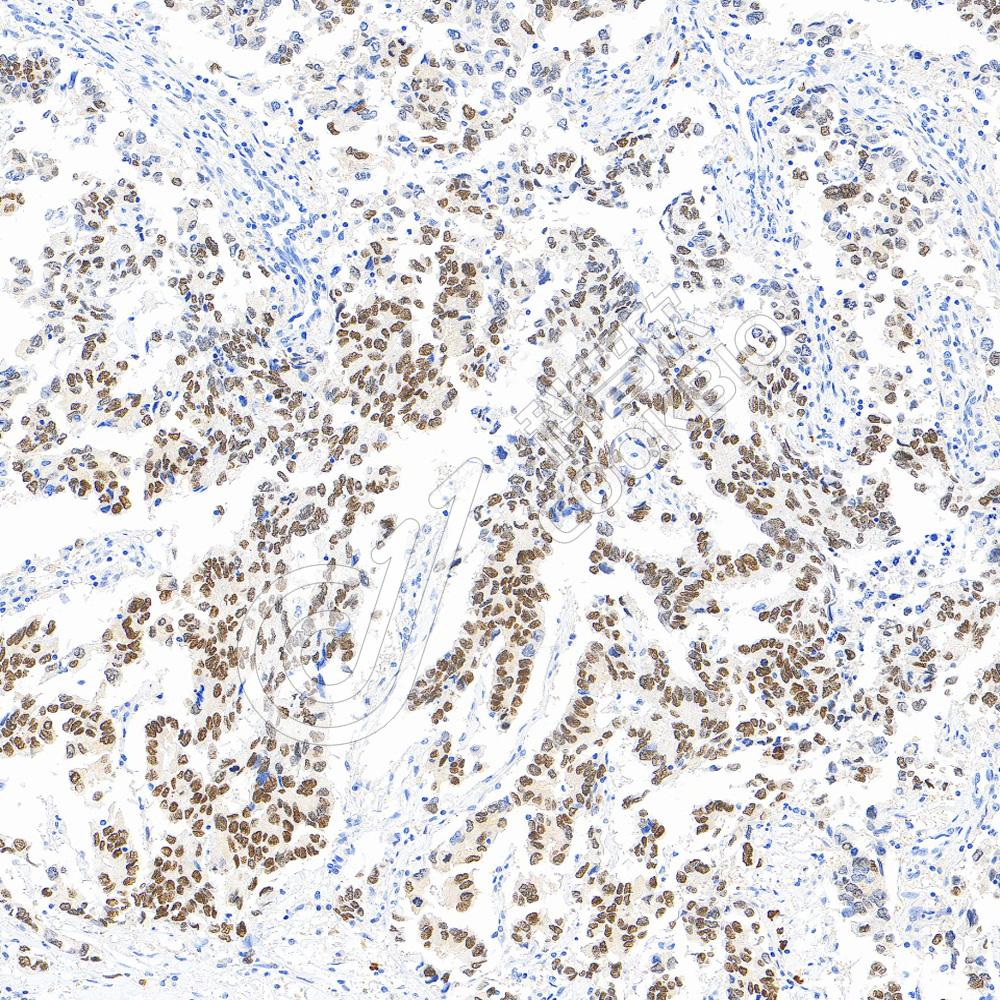

IHC检测CD8 alpha蛋白(货号 K5462588).

样品: 人结肠, 4%多聚甲醛 (货号KSG1101) 固定12-24小时.

抗原修复: 柠檬酸抗原修复液(干粉, pH 6.0) (KSG1201), 高压锅均匀喷气计时2分钟.

—抗: 1: 800稀释, 4℃ 孵育过夜.

二抗: S-vision免疫组化多聚二抗(山羊抗小鼠), 即用型(货号KB3903), 室温孵育20分钟.

样品: 人扁桃体, 4%多聚甲醛 (货号KSG1101) 固定12-24小时.